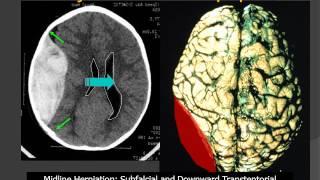

MedPix® Traumatic Brain Injury - Epidural Hematoma: Radiologic-Pathologic Correlation